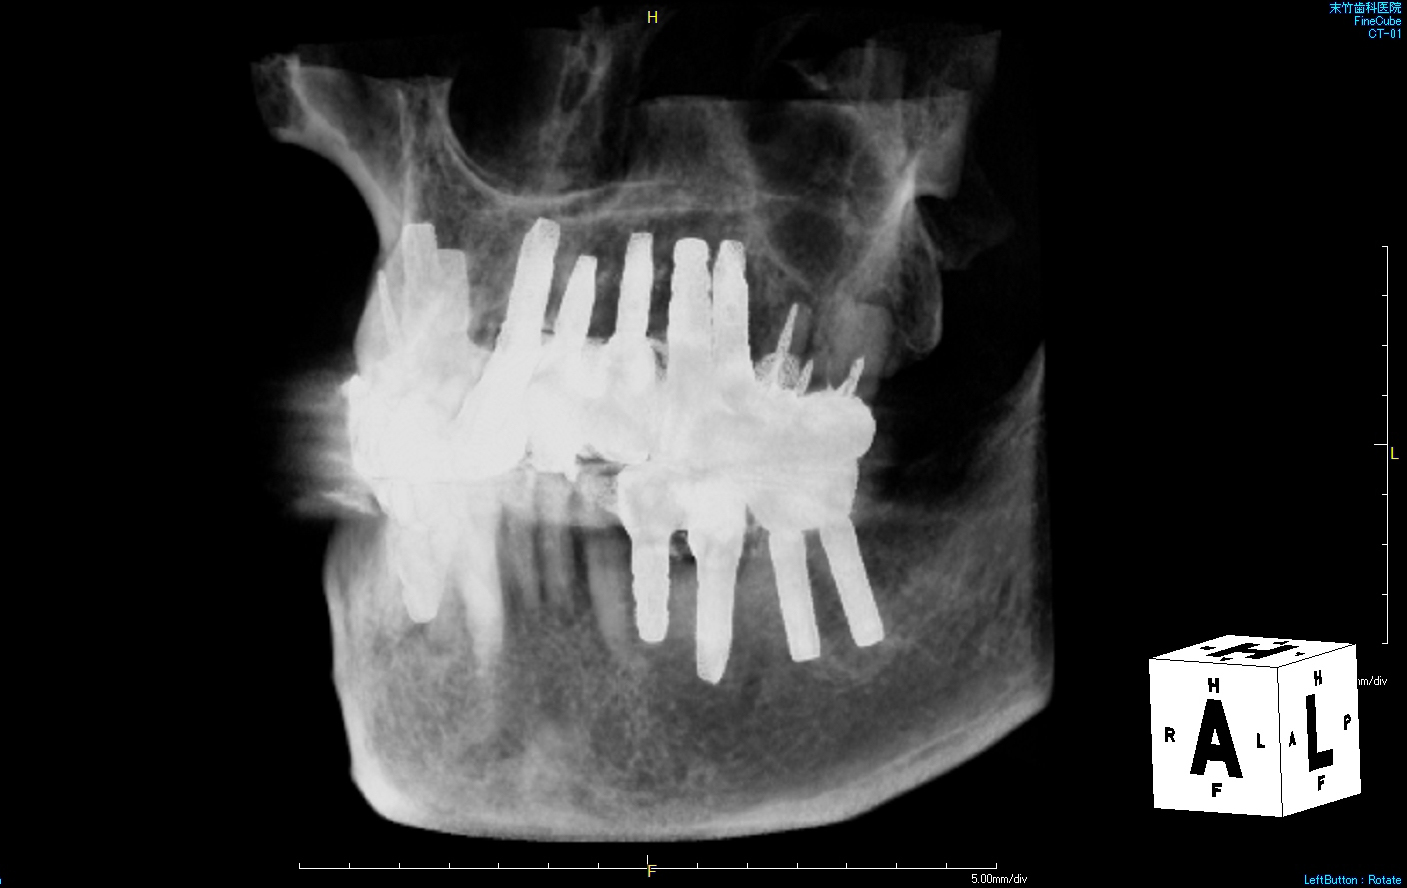

■ 自分の歯・・13本

■ インプラント・・15本

と、インプラントの方が2本多くなりました。

埋入ポジションや埋入深度などがそれぞれ異なりますので、CTで見ると何となく不揃いですが、24年経過するアストラテックインプラントをはじめとして、現在すべて良い状態です。